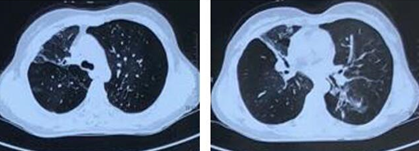

出院后在外院继续给予青霉素联合左氧氟沙星抗感染治疗1周,遂返家休养。2周后患者再次出现低热,但无明显咳嗽及呼吸困难。复查胸部CT示左肺下叶新发大片实变影,右肺上叶后段新发斑片状渗出伴结节影,右肺中叶实变影无明显变化(图5)

图片

图5  患者胸部CT

治疗10天后再次复查胸部CT:左下肺病灶范围较前明显增大,同时右肺上叶后段、下叶背段新发斑点状渗出、实变影(图6)

图6  患者胸部CT